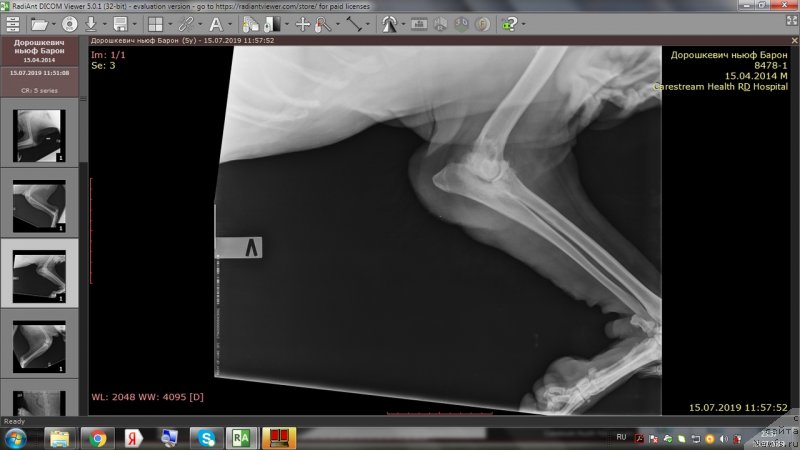

На приёме у врача.

Фотография № 243974

Фотография № 243976

Фотография № 243977

Фотография № 243978

Доброе утро,уважаемые форумчане!Вот и проползли черепашкой эти томительные 2 недели до повторного приема врача.И,вновь,к нашей радости,не подтвердились самые худшие опасения😊.Барошенька похудел на 3 кг.На снимках,как видно,в более-менее живом состоянии только правое колено.Локти не сгибаются из-за махровых наростов,с левым коленом ситуация хуже остальных лап,на прогулке,после лежания,первые несколько метров в колене слышно перестукивание суставов,но потом все проходит.Лечение идёт на пользу,колени стали лучше сгибаться,огромный отёк с левого колена спал,и писает теперь не приседая полностью до земли и не плюхаясь пузом от усталости в свою лужу.На прошлой неделе созванивались с доктором и немного подредактировали терапию-отменили тобрекс,т.к.не было результата и заменили на офтагель,флоксал,в связи с тем ,что у Бароши синдром сухого глаза и заворот века(рекомендовано в будущем провести операцию).Сегодня обновлю запасы этих лекарств.Антибиотик доксифин продлили до 8 недель,но купила пока на 2 недели,т.к.финансов не хватит на такой курс.Полное,качественное восстановление займет месяца 2.Сейчас то тут,то там выскочит экзема,соскоб с экзем показал наличие грибов-коки,эзофилы.Тут и стресс перенесенный и смена климата и т.д.

Вера, а артроскопию не предлагали? Так называемую санационную?

Я одной из своих собак делала. Чистили локтевые суставы, убрали мелкие отломки, туда противовоспалительный коктейль. Хромать стали намного меньше

Bonny2009,да,почитала сейчас в инете.Позвоню,спрошу у доктора завтра.Вчера нам ещё крупно повезло,что мальчика смотрела не только курирующий врач,но и сама Алексашина О.А.приходила,смотрела снимки,Барошу осмотрела,потискала😊 и оставила свои рекомендации.

У любой артроскопии есть конечно один недостаток - сустав начинает "цвести". Это мне объяснял человеческий доктор, зав. кафедры травматологии, ортопедии и медицины катастроф в Сеченовке, профессор Кавалерский Геннадий Михалыч. Он под этим словом подразумевал ухудшение впоследствии артроза и артрита. Но именно что впоследствии. Через несколько лет. Для человека это актуально, а для собак не настолько, потому что жизнь к сожалению короче...